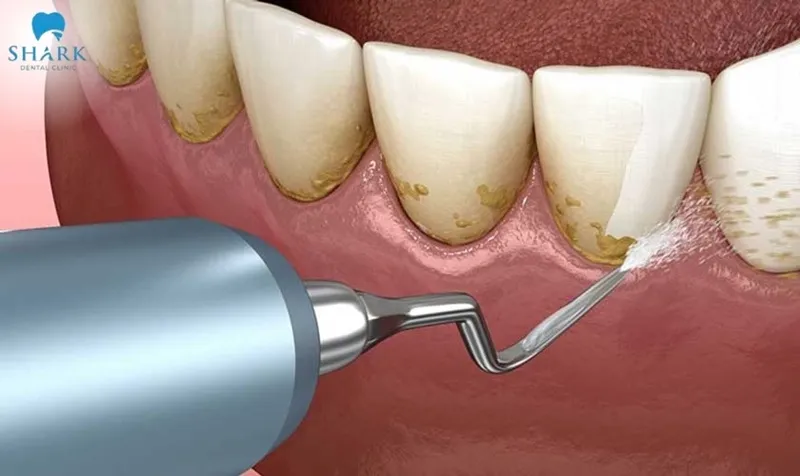

Dental scaling is a recommended method to keep your teeth and gums clean and healthy, but many people still hesitate because they are unsure whether it is safe or because they experience sensitivity afterward. So, is scaling good for teeth? To receive a clear and detailed explanation of this question, let Shark Dental Clinic guide you through the article below!

Many people tend to skip their routine teeth scaling appointments because they are unsure if scaling is beneficial for their teeth. In reality, dental scaling is a crucial step in oral care. It helps remove stubborn plaque, prevent gum inflammation, and maintain strong, healthy teeth over the long term.

Thanks to modern technologies such as ultrasonic teeth cleaning, the scaling procedure is now almost painless, safe, and does not harm the enamel. To achieve optimal results, it is recommended to have your teeth scaled every 4–6 months, depending on your dental condition, diet, and your dentist’s advice.

Dental scaling not only cleans the teeth but also plays a vital role in maintaining strong, healthy teeth and gums. The key benefits of removing tartar include:

Preventing gum disease

Long-term tartar buildup allows bacteria to accumulate, leading to gum issues such as inflammation, redness, bleeding, and discomfort. Scaling removes this stubborn plaque, reduces gum inflammation, prevents periodontal disease, and protects the tooth roots from bone loss. Healthy gums provide better support for teeth, which helps maintain normal chewing function and reduces the risk of serious oral diseases.